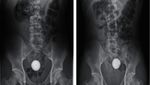

Balita berusia 4 tahun di Taiwan dilaporkan tidak sengaja menelan koin besar. Setelah 28 hari berada di dalam perutnya, koin tersebut berhasil keluar berkat bantuan obat pencahar yang diresepkan dokter. (Foto: International Journal of Emergency Medicine)